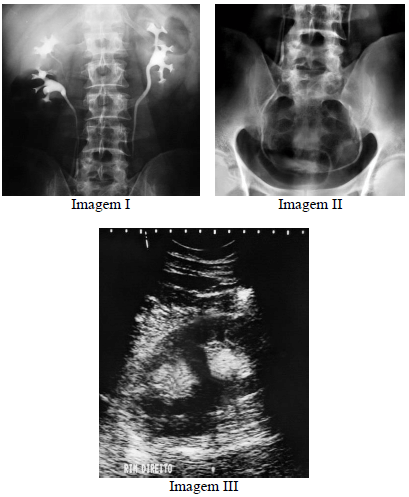

Considerando o diagnóstico evidenciado nas imagens precedentes, julgue o item a seguir.

A imagem III demonstra sinais típicos de duplicação pielocalicinal, sendo a ultrassonografia um método com alta sensibilidade, estimado em cerca de 90% para detecção dessa entidade.

A entidade demonstrada nas imagens está associada a aumento de incidência de estenose da junção ureteropélvica e de outras malformações geniturinárias.